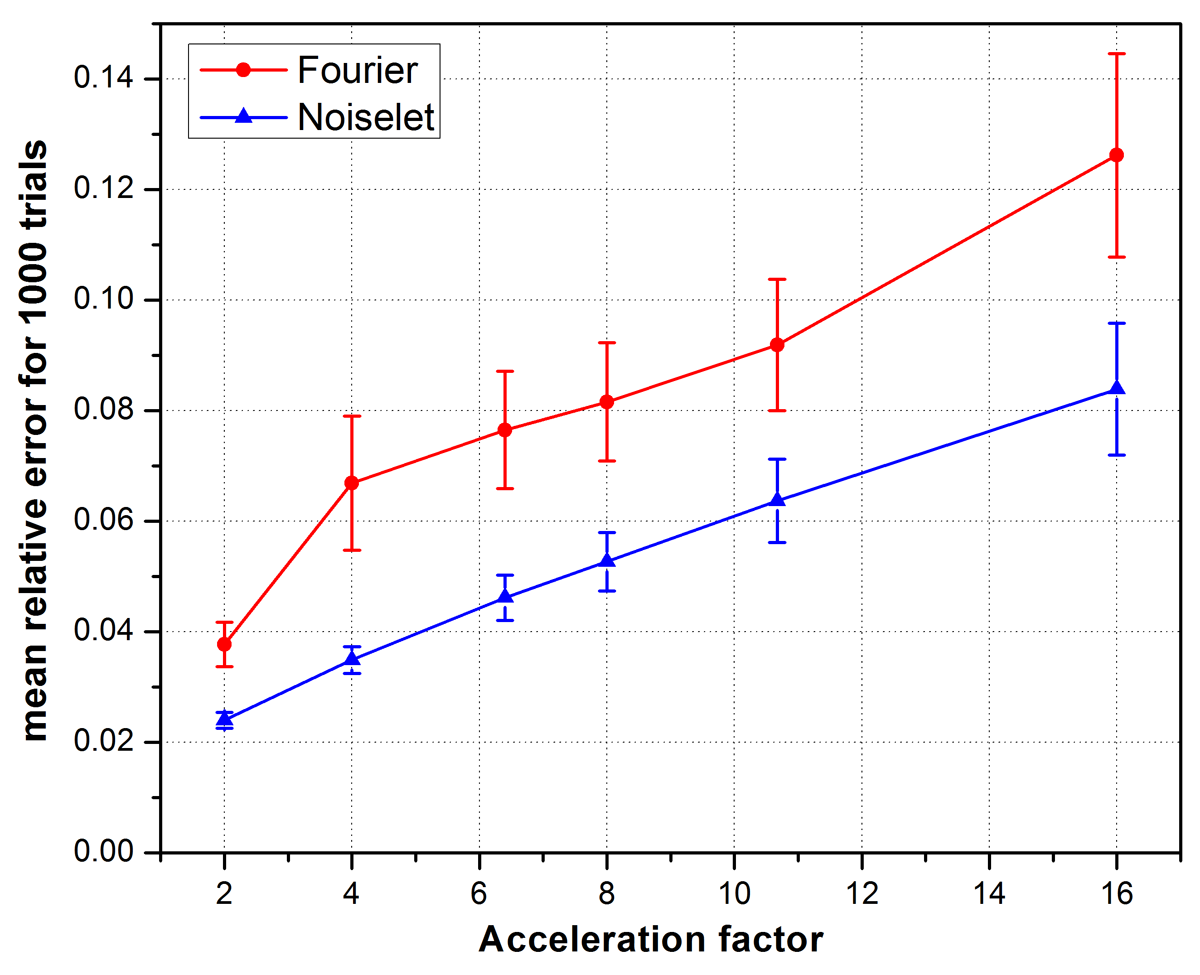

To measure the relative error, simulations were performed on the brain image for 1000 times by randomly generating a sampling mask each time. The mean of the relative errors was calculated after 1000 such reconstructions at every acceleration factor. The mean relative error versus the number of measurements is plotted in Fig. 9 and highlights that noiselet encoding outperforms Fourier encoding for all acceleration factors. The relative error for noiselet encoding at an acceleration factor of 16 was the same as the relative error for Fourier encoding at an acceleration factor of 8 indicating that higher acceleration factors are achievable with noiselet encoding compared to Fourier encoding.

6 Discussion

We have presented a new method of encoding the MR data in PE direction with noiselet basis functions for accelerating MRI scans using MCS-MRI reconstruction. The simulation results demonstrate that the proposed encoding gives rise to a multichannel measurement matrix with improved RIP, and the reconstruction method using the noiselet bases outperforms the conventional Fourier encoding scheme. The mean relative error for noiselet encoding at the acceleration factor of 16 is comparable to that of Fourier encoding at the acceleration factor of 8, demonstrating that higher acceleration factors can be achieved with noiselet encoding than the Fourier encoding in the MCS framework.